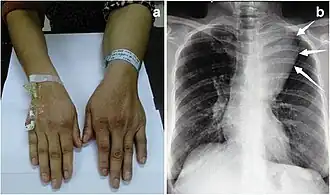

O angiolipoma geralmente se manifesta como muitos nódulos subcutâneos dolorosos (solitários em apenas um terço dos pacientes), mais comumente originados nos membros superiores (dos quais o antebraço representa cerca de dois terços), no tronco e nos membros inferiores.[3][4] Essas lesões são bem definidas, geralmente medindo menos de 4 cm.[5]

- ↑ Hassan, Hunar A.; Hassan, Hemn A.; Ali, Rebwar A.; Omar, Diyar A.; Salih, Abdulwahid M.; Kakamad, Fahmi H. (2022). «Multiple angiolipoma of the hand, back, and abdomen; a case report». Elsevier BV. International Journal of Surgery Case Reports. 93: 106901. ISSN 2210-2612. PMC 8927707